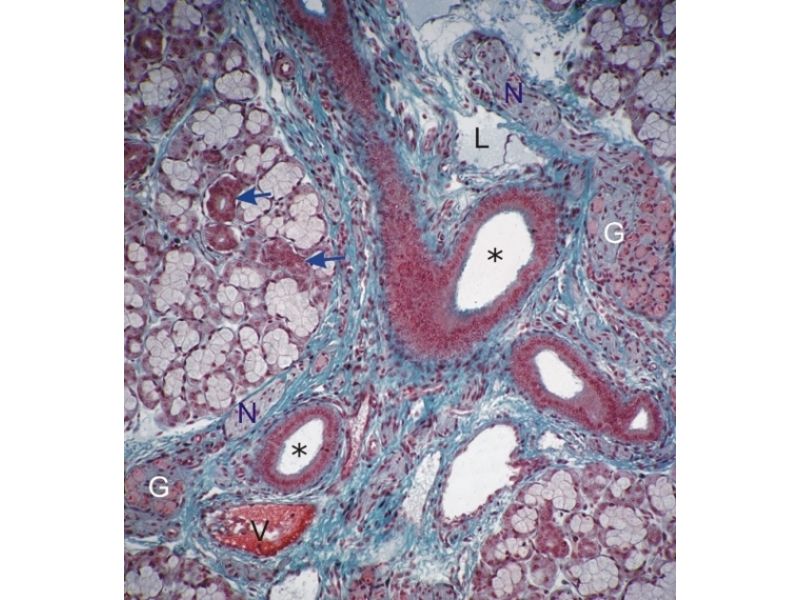

Mammary Gland and Nipple

Mammary gland - slide 57